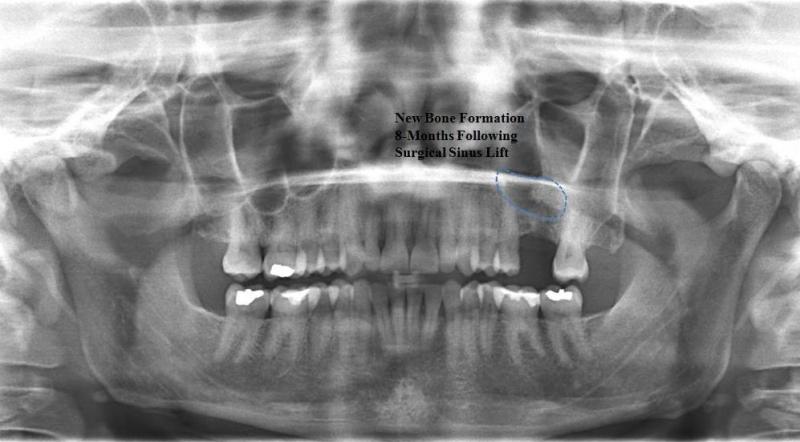

Dento-alveolar surgery (impacted teeth like wisdom teeth and canines, difficult tooth extractions, extractions on medically compromised patients, apicoectomy, bone grafting/bone harvesting or pre-prosthetic surgery) (See Images Below)

Surgery to insert osseo-integrated dental implants and Maxillofacial implants for attaching craniofacial prostheses (See Images Below)